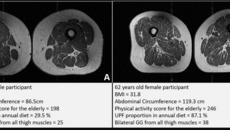

초가공식품 많이 먹었더니…허벅지 근육에 ‘마블링’ 형성[바디플랜]

스탠퍼드대 의대 면역학·류마티스학과 타미코 가츠모토 교수는 NBC뉴스와 인터뷰에서 “근육 지방 축적은 허벅지에만 국한되지 않을- 2026-04-16 12:02